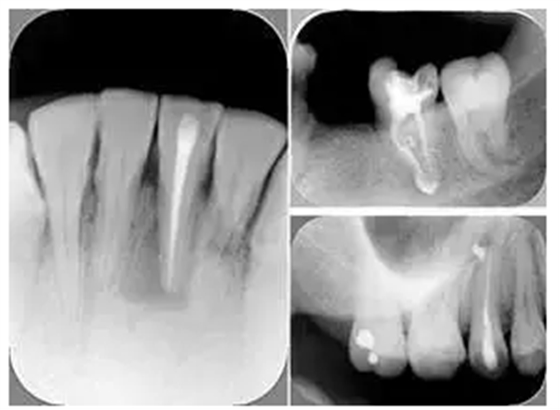

2. X 線片

共有 4 張 X 線片,分別是術(shù)前、診斷絲 、主牙膠尖確認(rèn)、術(shù)后。

( 1 )術(shù)前:術(shù)前 X 線片用來了解牙齒的大概情況。術(shù)前預(yù)期為多根牙時(shí) X 線片應(yīng)偏頭拍攝。

( 2 )診斷絲:根據(jù)術(shù)前 X 線片進(jìn)行開髓、根管的初步預(yù)備后,需要插入診斷絲,用來指示工作器械位置。常用 10 號或 15 號擴(kuò)大器作為診斷絲插入牙髓腔。

( 3 )主牙膠尖確認(rèn):通過術(shù)前預(yù)期和診斷絲診斷,明確工作長度、牙根走向,進(jìn)行根管預(yù)備。之后應(yīng)進(jìn)行主牙膠尖(中銼)確認(rèn),已明確根管是否適合充填。

( 4 )術(shù)后:觀察治療效果。

根管初步預(yù)備完畢后用 H 銼提拉,之后進(jìn)行工作長度再確認(rèn)。插上牙膠尖,拍攝 X 線片,觀察主牙膠尖位置。

術(shù)后 X 線片用來評定根管充填 長度、致密度(管壁清晰、側(cè)枝)等指標(biāo)。

左圖為根管充填術(shù)后 X 線片。圖中可見,根管充填較好。右下圖有白色小點(diǎn),為側(cè)方加壓導(dǎo)致糊劑擠出所致,表明根管充填比較致密。